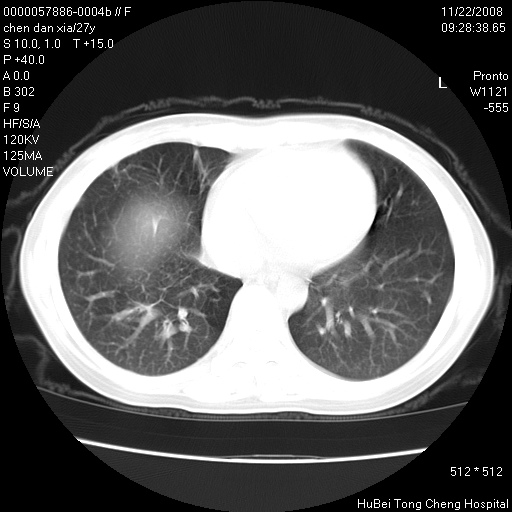

标题: CT16752:F,27Y。发热咳嗽20余天,伴盗汗。 [打印本页]

标题: CT16752:F,27Y。发热咳嗽20余天,伴盗汗。

考虑双肺粟粒性肺tb,右侧胸膜增厚.

气管前腔静脉后淋巴结肿大 右肺门纹理模糊

淋巴结核?

右下肺见片絮状影,两肺野内分布不均的小结节影,结核并肺内播散可能性大,建议结合实验室检查 .

右下肺纹理模糊;纵隔可见肿大淋巴节;右心缘旁结节,边缘光滑,纵隔窗病变范围较肺窗明显小,首先考虑右下肺结核,不排外淋巴瘤

双肺纹影普多,部分呈网状,支炎或淋巴管炎?

纵隔内淋结肿

局部胸膜增厚

下肺结节,结节内钙化,肺门纵隔淋巴肿大 结核可能性大

似有粟米状结节。考虑粟粒型肺结核?

1)考虑两肺感染性病变。2)纵隔淋巴结肿大。